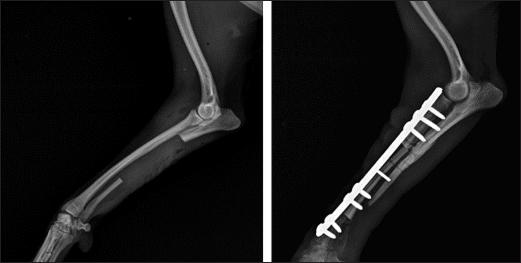

То harvest the autogenous cortical graft, a caudal approach to the contralateral ulnar diaphysis was used (Fig. 2). The subcutaneous tissue was bluntly dissected, and thereafter retraction was maintained using Gelpi retractors. A Hohmann retractor was placed between the ulna and radius to prevent iatrogenic damage to the radius. A 4.8 cm long bone segment of the ulnar diaphysis was removed by means of an oscillating saw. The ostectomy and periosteum were removed en bloc and transferred into the surgical gap of the right radius. At both ends of the cortical autograft, a cancellous graft soaked with 1,000 IU recombinant human erythropoietin (Binocrit®, 2000 IU, Sandoz GmbH, Kundl, Austria) was applied for optimization of osteoinduction and angiogenesis. To collect the cancellous graft, a small incision was made over the craniolateral aspect of the greater trochanter. A 3.5-mm hole in the proximal humeral metaphysis was created with a drill bit and a bone curette was used to harvest the cancellous graft. Then, it was inserted into the recipient site as soon as possible to minimize cell death. After proper alignment of bone fragments, they were fixed with a dynamic compression plate (1.5 mm thickness) and 8 cortical screws: 2 in the distal radial fragment, 3 in the cortical graft, and 3 in the proximal radial fragment (Fig. 3). The intradermal layer was closed with an absorbable monofilament suture material (PDX, 3-0, VetSuture, France), followed by non-absorbable skin sutures (Nylon, 3-0, Kruuse, Denmark).

Fig. 2. Collection of bone autograft after caudal approach to the contralateral ulnar dyaphysis (left) and placement of the bone graft in the radial defect (right).

Fig. 3. Mediolateral radiograph of antebrachial bones after the revision surgery. Left: the ulna of the healthy thoracic limb after harvesting of the cortical autograft. Right: fixation of the cortical autograft with dynamic compression plate.